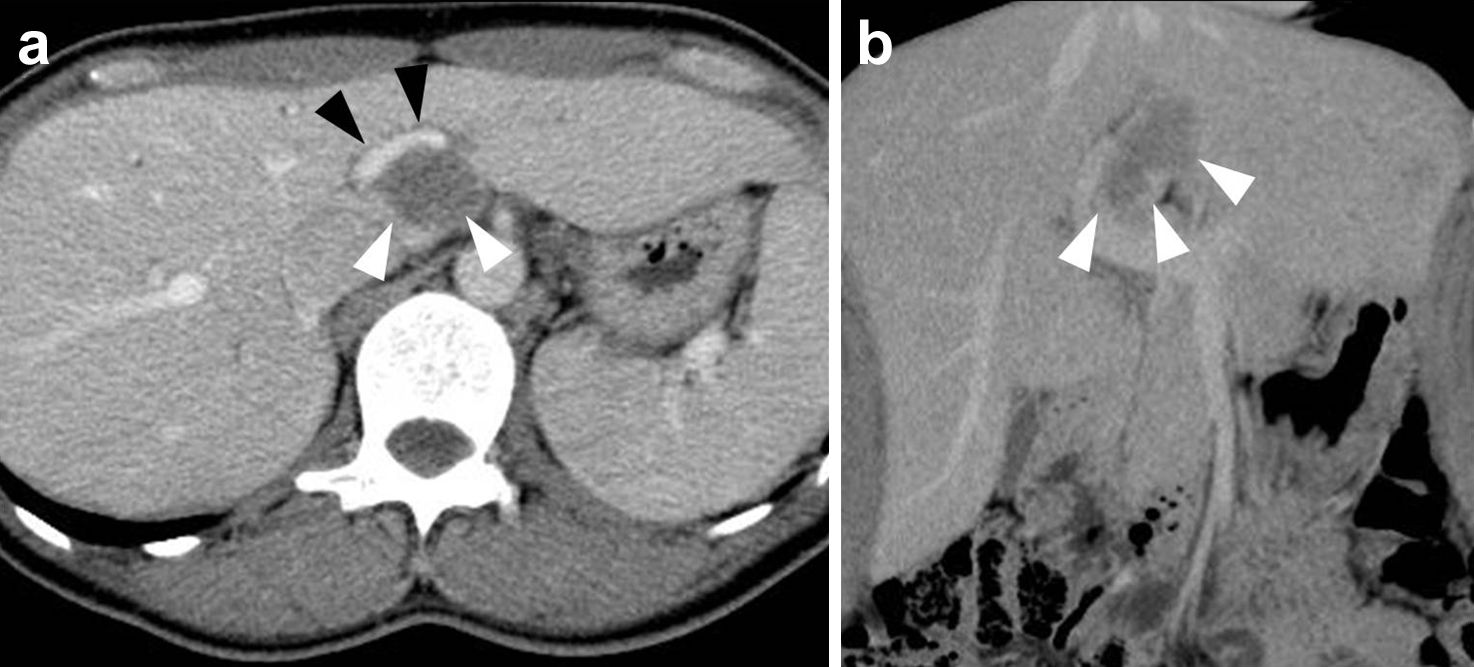

腹部造影CT所見(初診時):肝尾状葉腹側に造影効果に乏しい44×24×18 mm大の境界明瞭な腫瘤を認め,門脈左枝に接していた(Fig. 2).

(a, b) Abdominal contrast CT revealed a well circumscribed low density tumor of size 44×24×18 mm touching the left branch of the portal vein on the ventral side of the hepatic caudal lobe (white arrowheads: tumor, black arrowheads: left branch of portal vein).